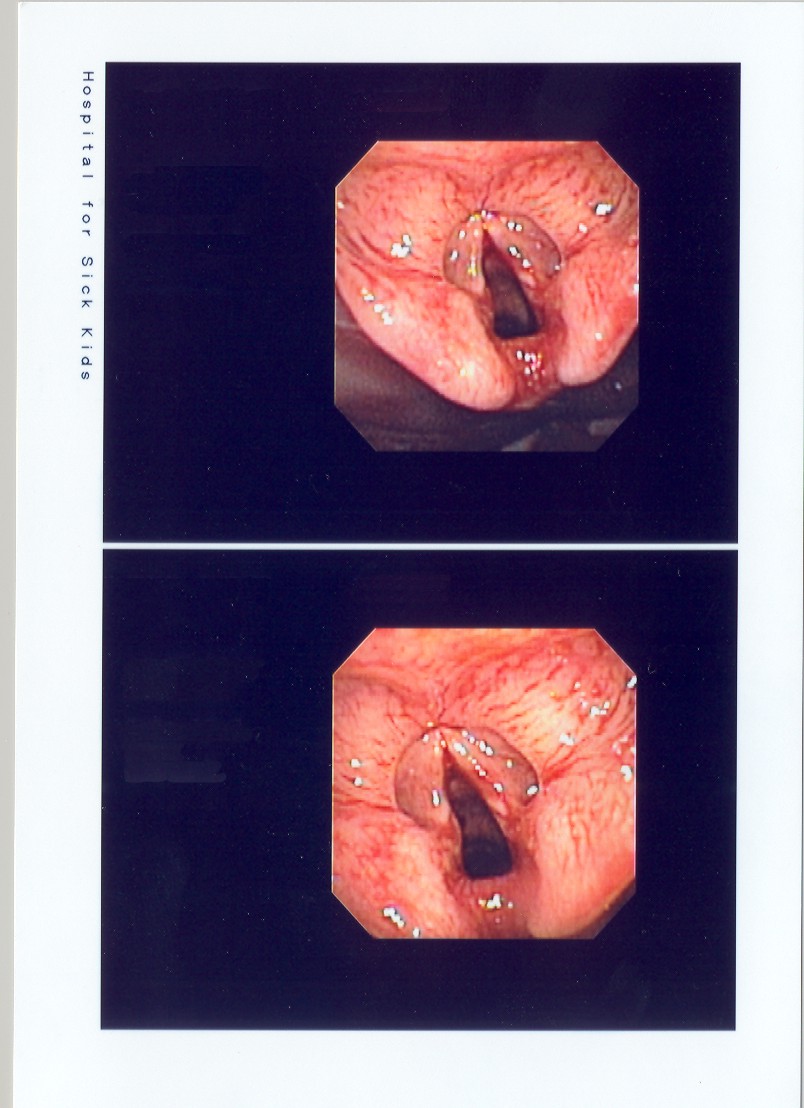

Images from the bronchoscopy are shown.

The next screen shows images from bronchoscopy: